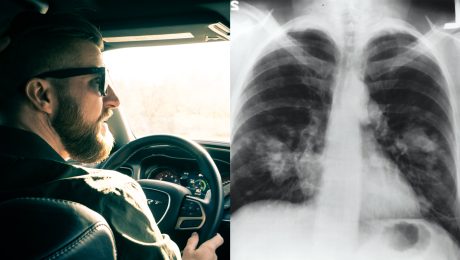

Nové auto si

Nové auto si pridlho neužívaj. Obľúbená vôňa ti môže privodiť rakovinu, varujú vedci